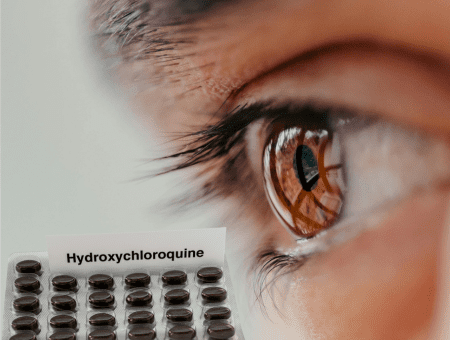

Hidroxicloroquina x Visão

Outubro 19, 2025

A hidroxicloroquina é usada para o tratamento da artrite reumatóide, lupus, doenças dermatológicas e malária.Seu